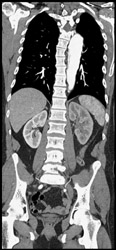

Superior Mesenteric Artery (SMA) Stenosis